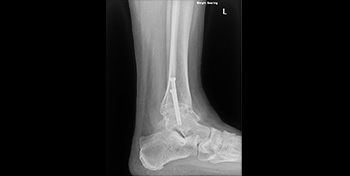

- Week 10 after surgery – Into normal shoes and physiotherapy. Picture showing successful fusion and internal metalwork